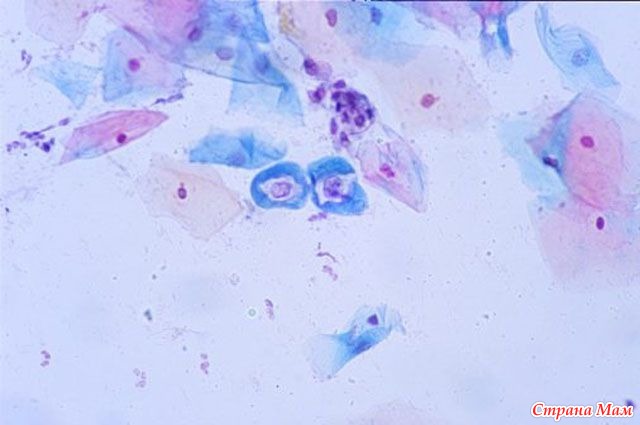

Во время скрининга обязательно проводится цитологическое исследование шеечных мазков (PAP – smeartest). По словам эксперта, объем скрининга может меняться в зависимости от возраста женщины (только PАР-мазок или РАР-мазок + исследование на ВПЧ).

Но его чувствительность неабсолютна: 66–83%. В 70–90% ложноотрицательные цитологические ответы случаются из-за низкого качества взятых мазков, в 10–30% налицо ошибочная интерпретация цитологических данных.